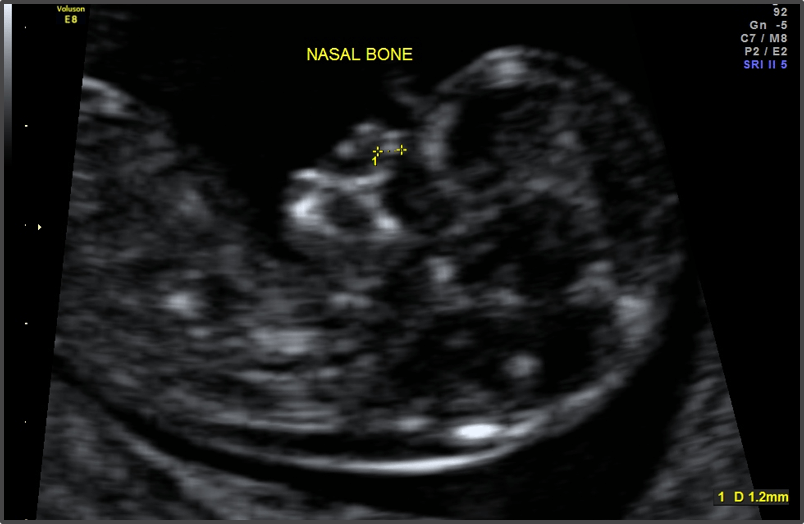

The baby is almost fully formed.

Approx Baby Size: 4.1 cm